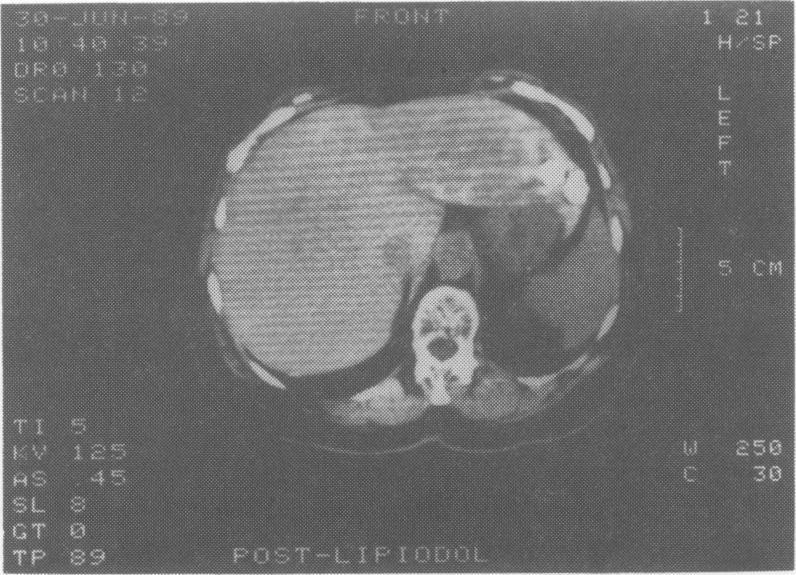

A case of recurrent hepatocellular carcinoma following resection is reported. The patient received 2 treatments of 131I-lipiodol administered via the hepatic artery at angiography. Good localization in tumour tissue was observed on subsequent computed tomographic scans and no adverse effects were seen after either treatment. After the first treatment 2 nodules of recurrent tumour were resected and proved to be totally necrotic. The patient remains well 9 months later with a persistently elevated serum alphafetoprotein but no evidence of residual tumour. It is suggested that 131I-lipiodol may be the treatment of choice for small tumours in elderly high-risk patients.

本文报告了1例肝癌切除术后复发的病例。该患者在血管造影时经肝动脉接受了2次131I-碘油治疗。在随后的计算机断层扫描中观察到肿瘤组织有良好的定位,且每次治疗后均未出现不良反应。第一次治疗后,切除了2个复发性肿瘤结节,病理证实完全坏死。9个月后患者情况良好,血清甲胎蛋白持续升高,但无残留肿瘤迹象。提示131I-碘油可能是老年高危患者小肿瘤的首选治疗方法。